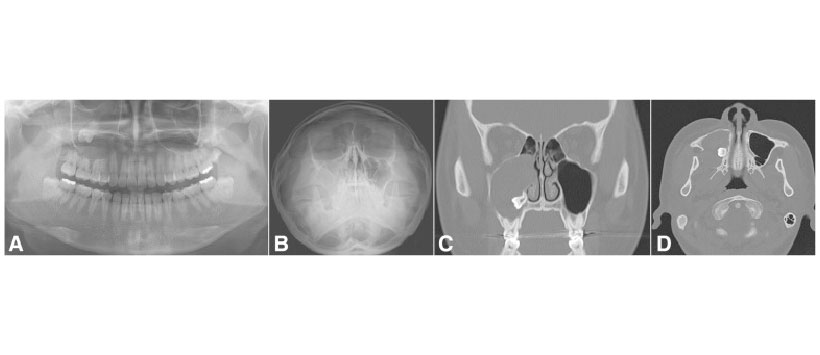

Figura 3: La fístula oronasal crónica después de la extracción del segundo molar con varios puntos de reabsorción ósea alveolar indica sinusitis maxilar odontogénica. Vistas panorámicas preoperatorias (a), de Water (b), TC coronal (c) y TC axial (d)